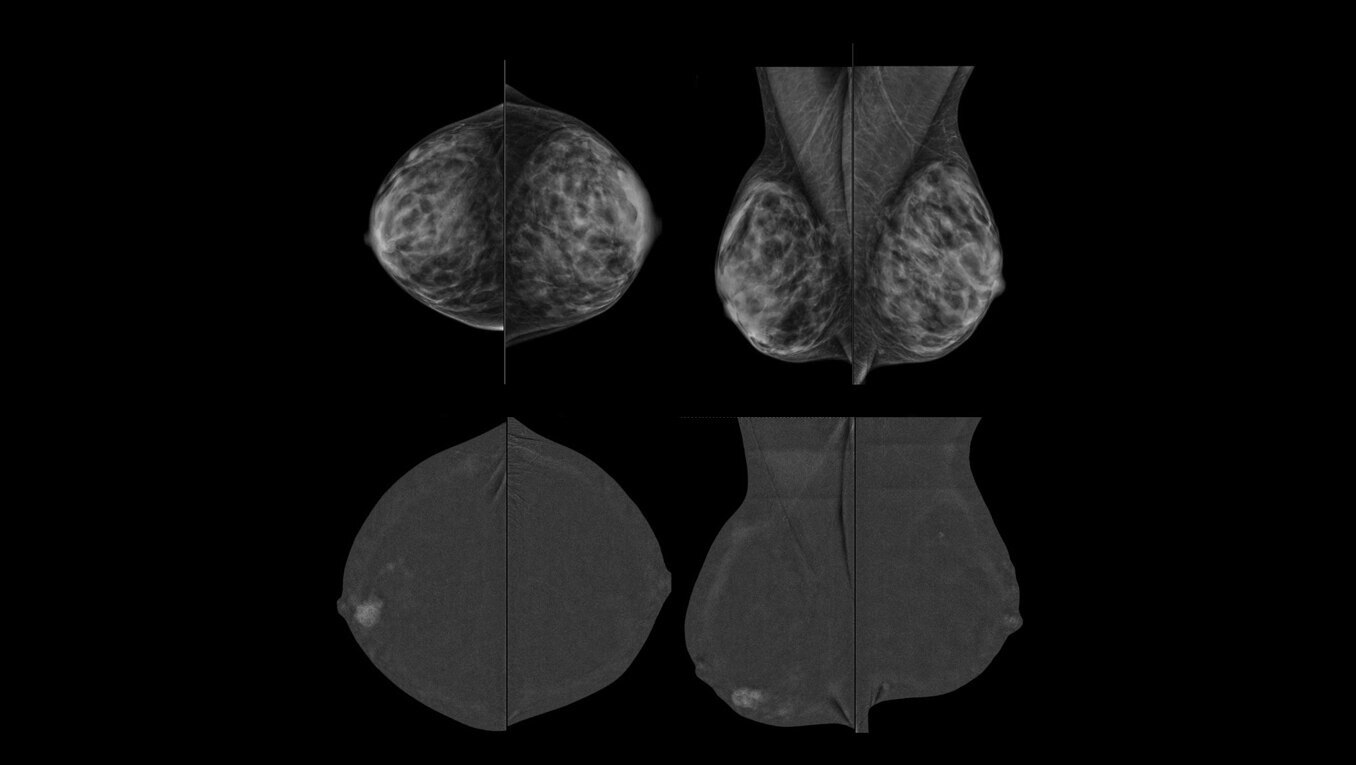

GE HealthCare pioneered this technology in 2010 and is associated with over 200 publications that demonstrate its clinical performance. GE HealthCare’s CEM combines the morphologic and density information similar to a conventional mammogram and the functional vascular information of a breast MRI1. It presents an opportunity to create and implement a more streamlined workflow to help diagnosis breast cancer early. In addition to increasing patient access, our CEM offering boasts high levels of sensitivity and specificity, allowing for the detection of lesions that would otherwise go undetected2,3,4. To ensure your practice can fully leverage the combined power of GE HealthCare contrast mammography solutions, we introduce Pristina Bright our comprehensive CEM package with complete support, from training to service, for your successful implementation.